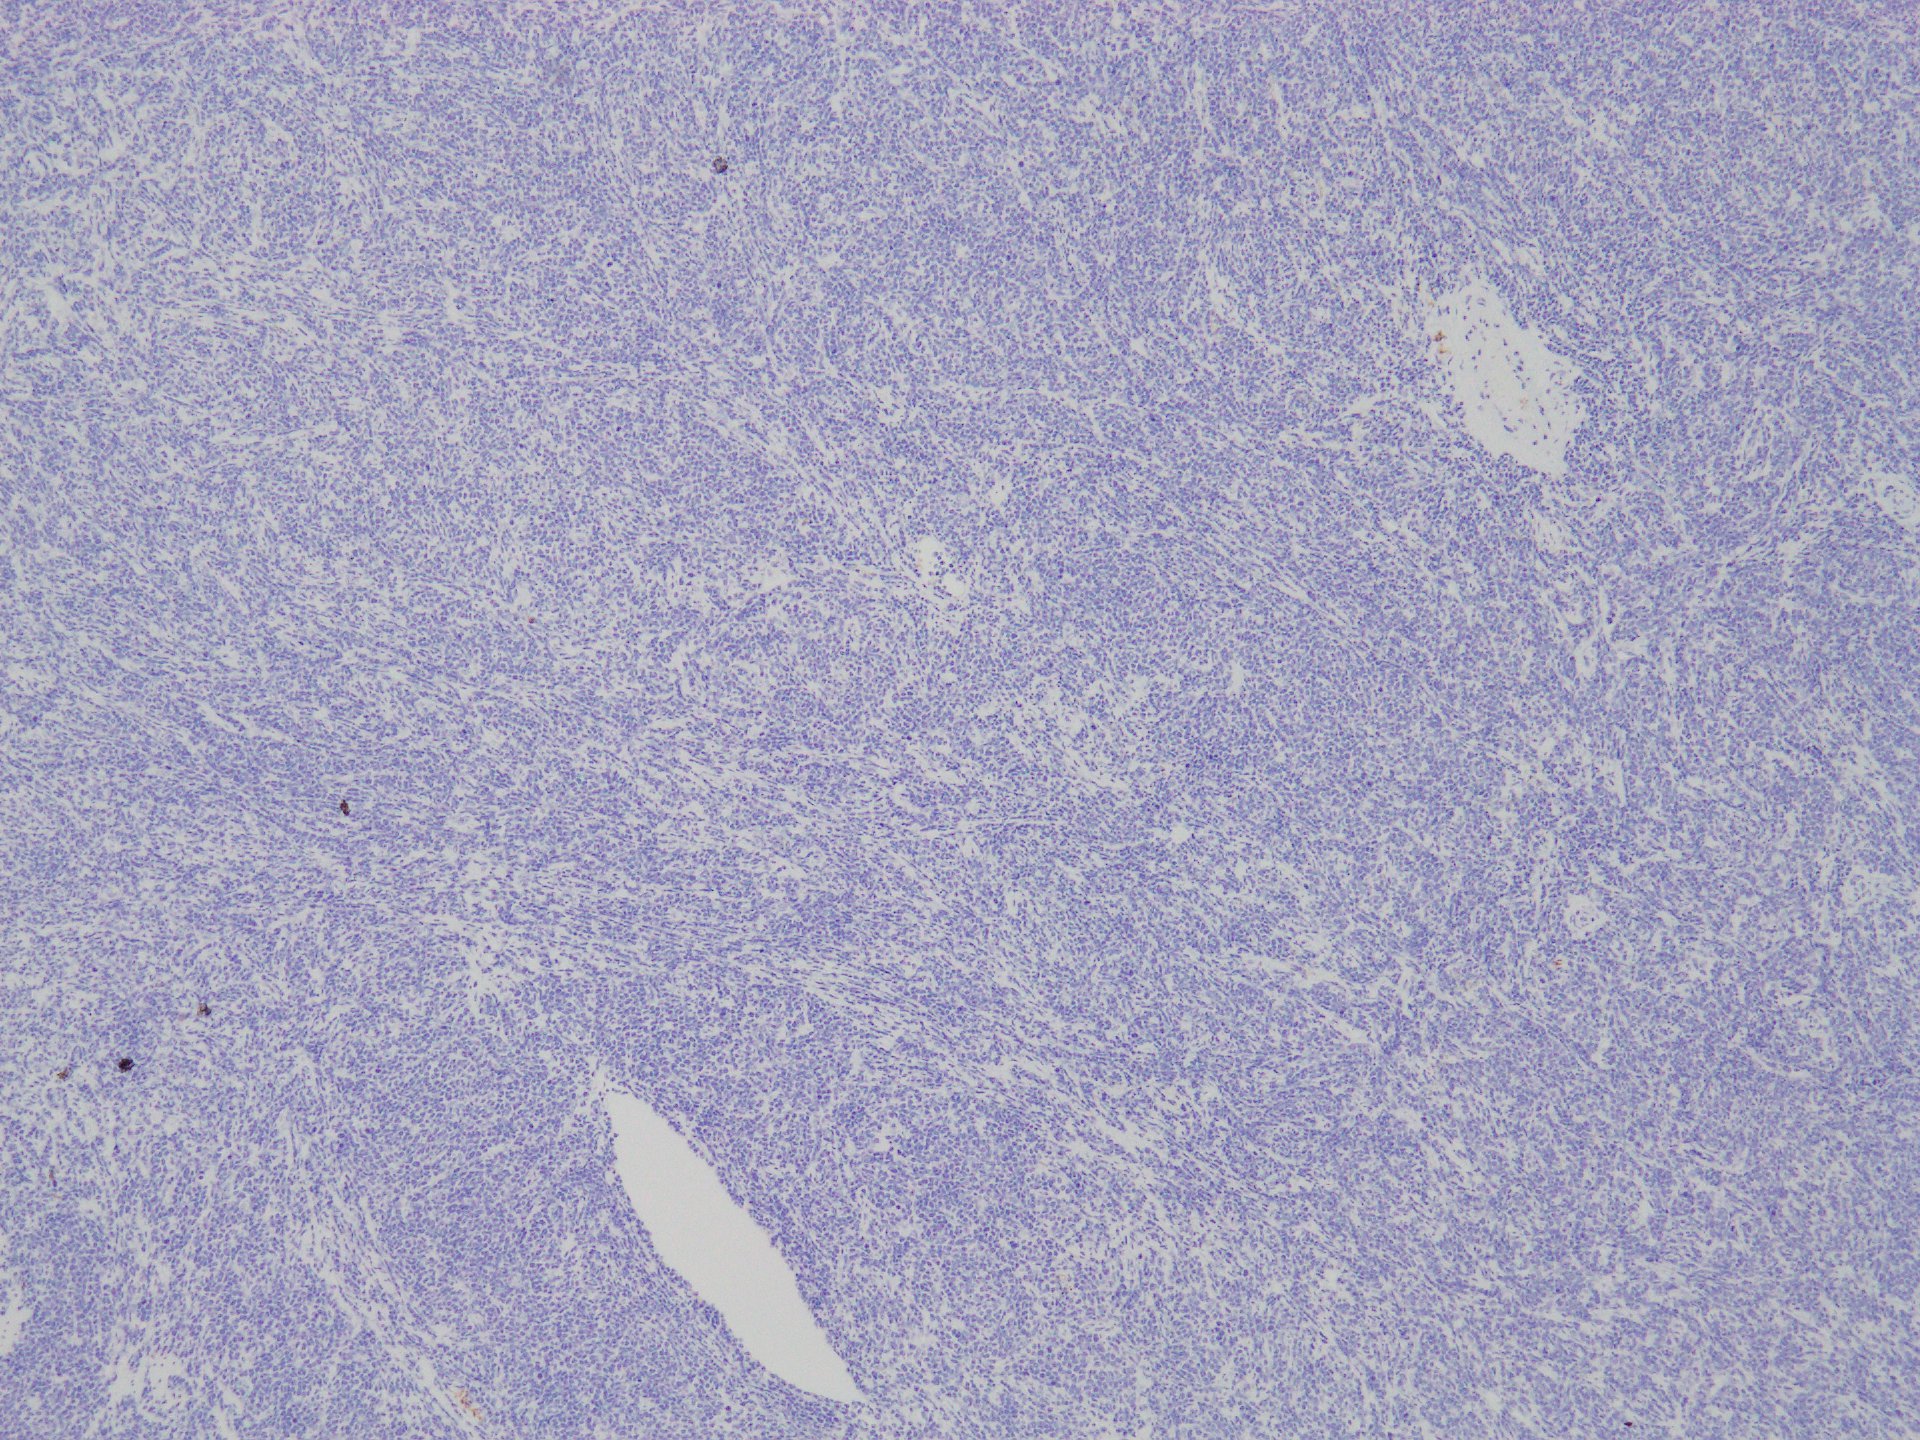

HE loupe像

loupe像では, 腫瘍細胞が髄様密に浸潤増殖する部位と, 精細管をスペアするように管間に腫瘍細胞が浸潤する部分(右端図 A)がある.

切り出し図とは天地を逆にした右端図では, 髄様密な部分は白膜内で増殖するリンパ腫瘤(B)であることがわかる. 精巣上体の一部に浸潤がみられる(C)

精巣実質

lympho-tubular lesion

loupe像Aの領域: 精細管をスペアするように, 小型リンパ球優位, 一部中型のlymphoid cellsがシート状密に浸潤増殖する. tubulesのほとんどにはlymphoid cellsが浸潤していないが, LELに似たようなlympho-tubular lesionが少数認められた. x400高倍率では, 増殖細胞は, 粗く, 凝集したクロマチンをもつ類円形, non-cleavedな核をもつ細胞質の乏しいlymphoid cellsである. 核小体か凝集したクロマチンかわかりにくい.